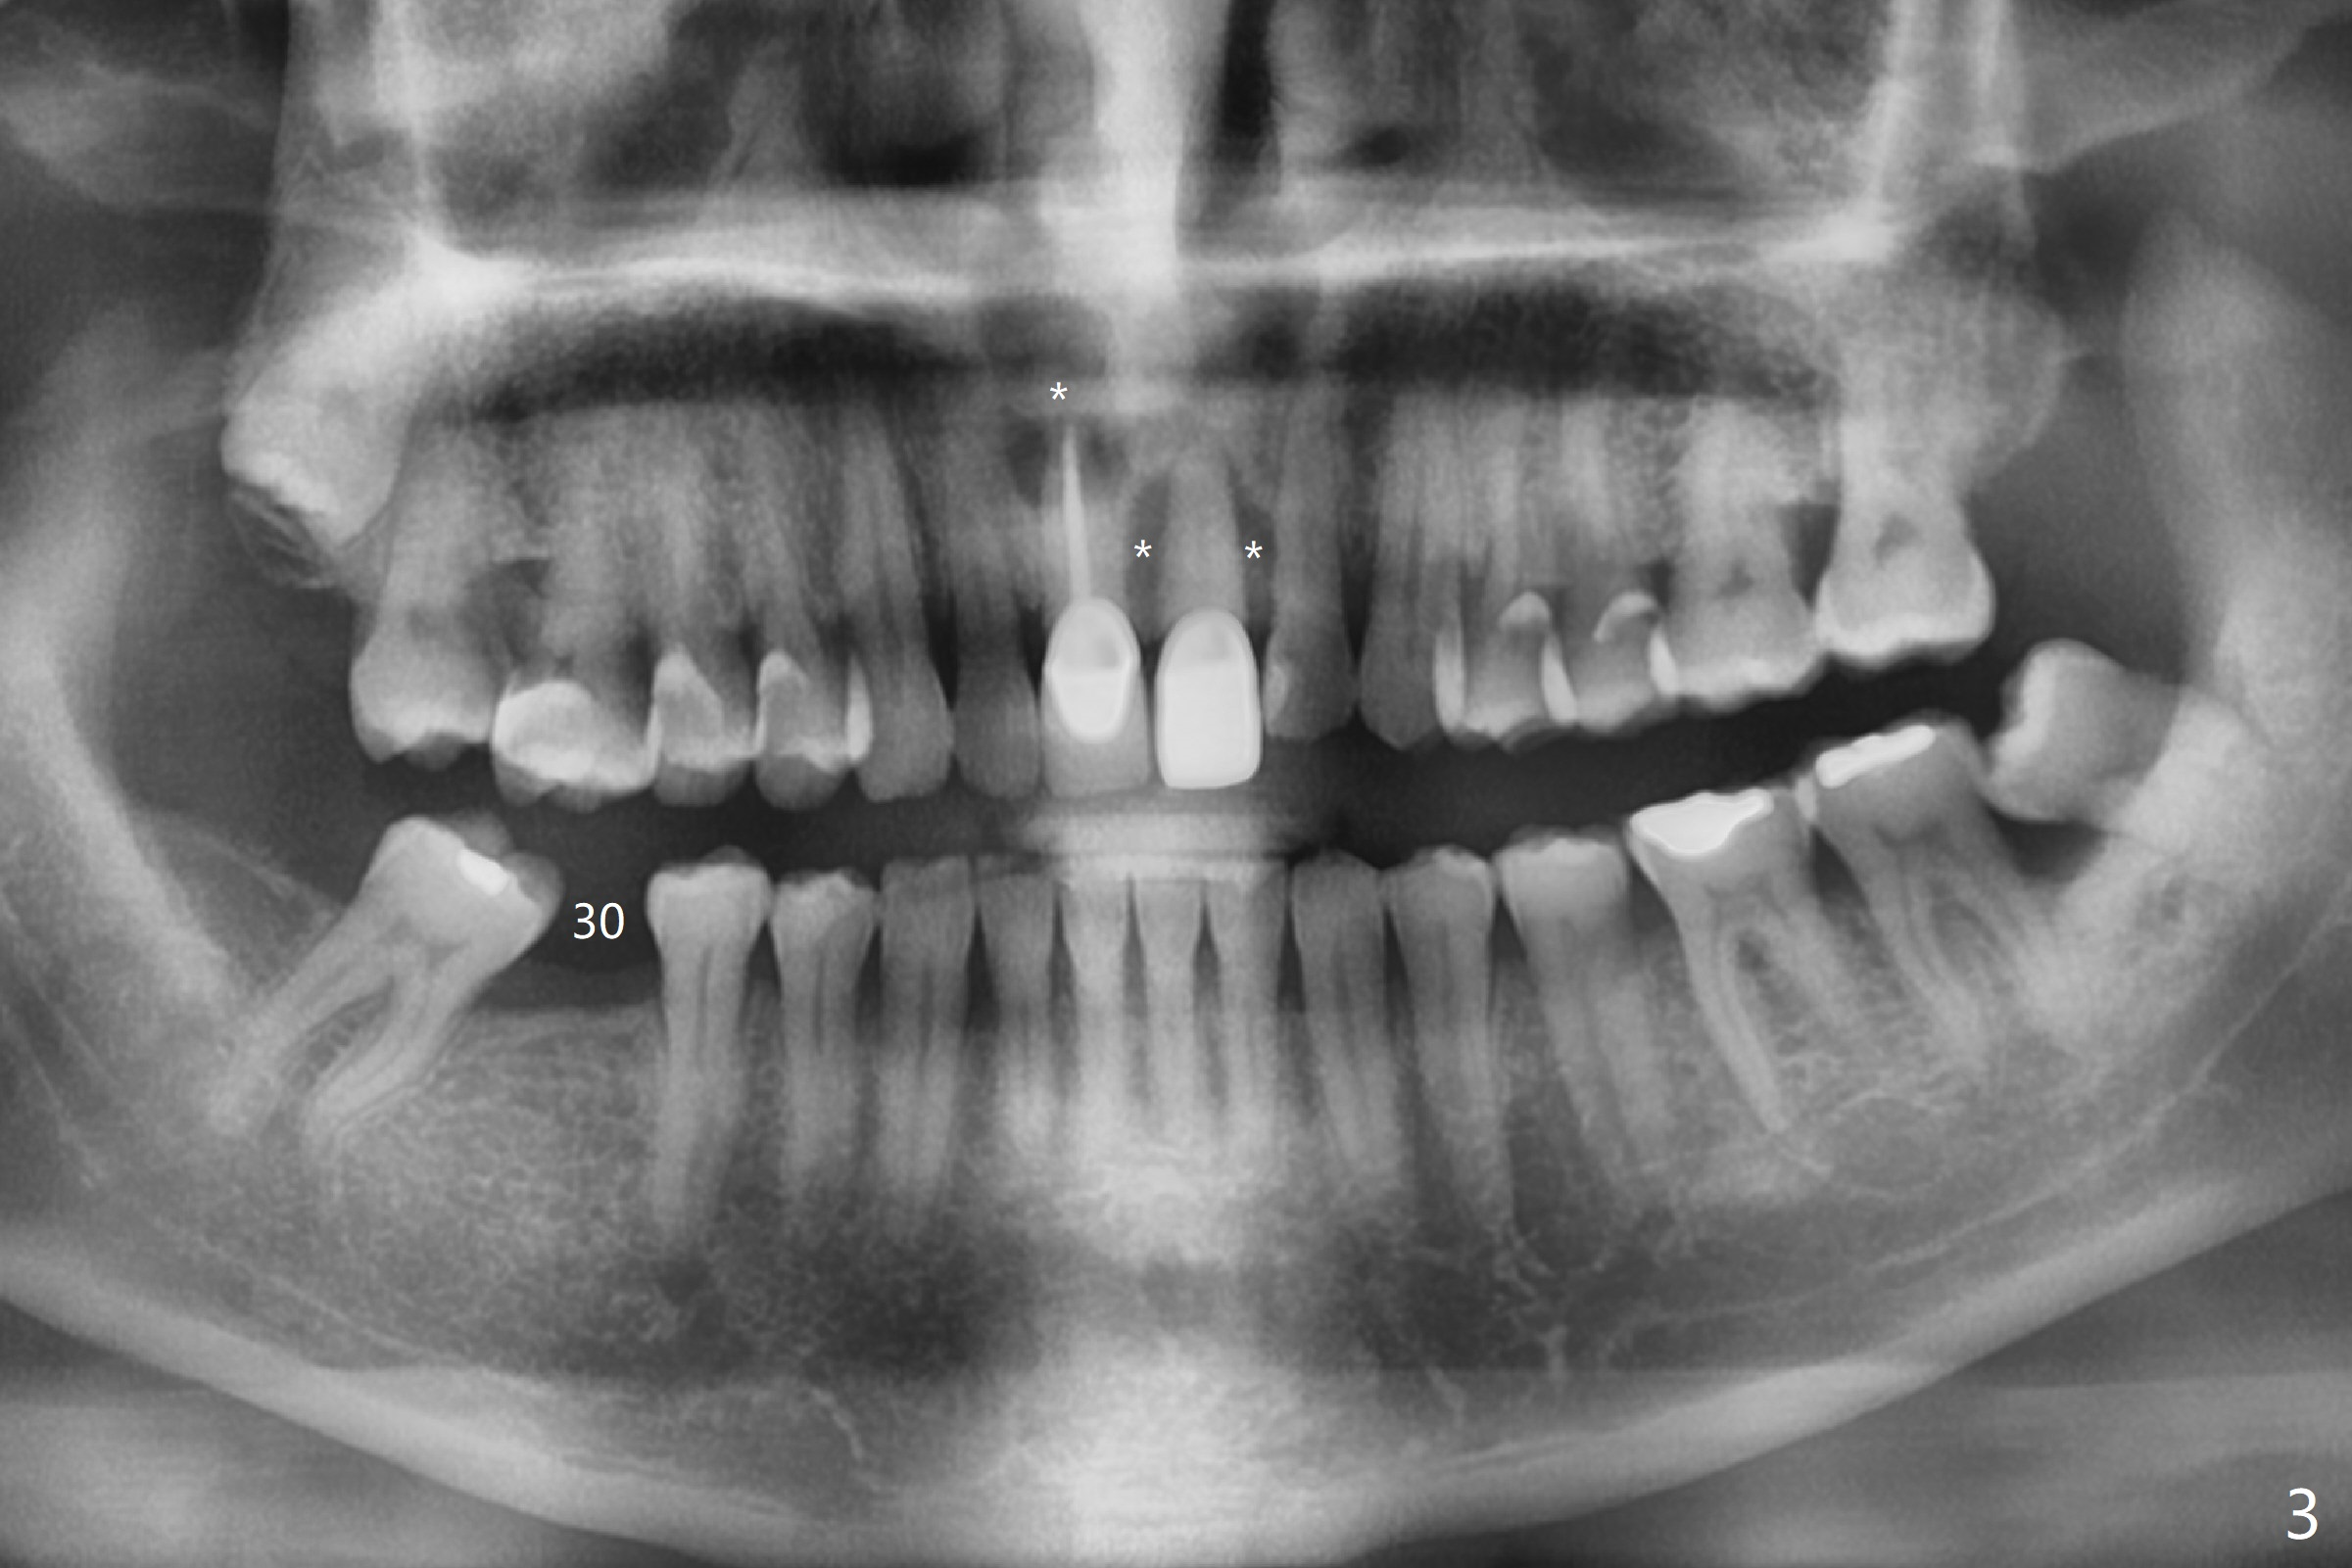

A 55-year-old man does not like the extruding tooth #9 (Fig.1,2). While there are fistulae associated with the two central incisors (arrowheads in Fig.1,2), bone loss appears to be apical at #8 and crestal at #9 (Fig.3 *). To avoid iatrogenic bone loss associated with two neighboring implants in the cosmetic zone, apicoectomy is to be performed at #8, while an immediate implant will be placed at #9 with guide at the same time (Fig.4). Furthermore there is missing or thin buccal plate at #8 (Fig.5 B).